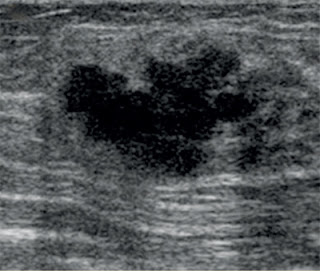

Achados:

- Qualquer nódulo sólido com:

o Margens não-circunscritas (indefinidas, anguladas, microlobuladas ou espiculadas).

o Atenuação acústica posterior (que não seja um fibroadenoma calcificado típico na mamografia).

o Eixo vertical (mais alto que largo).

o Calcificações finas em seu interior.

o Padrão ductal em sua periferia ou padrão ramificado.

o Hiperecogenicidade em suas margens.

o Forma redonda e muito hipoecóico: nestes casos podemos fazer punção com agulha fina para excluir a possibilidade de cisto com conteúdo espesso.

- Cistos complexos:

o Com septos ou paredes espessadas.

o Com componente sólido no interior.

- Lesões intraductais.

- Áreas de atenuação acústica.

- Áreas sólidas com limites pouco definidos e textura heterogênea.